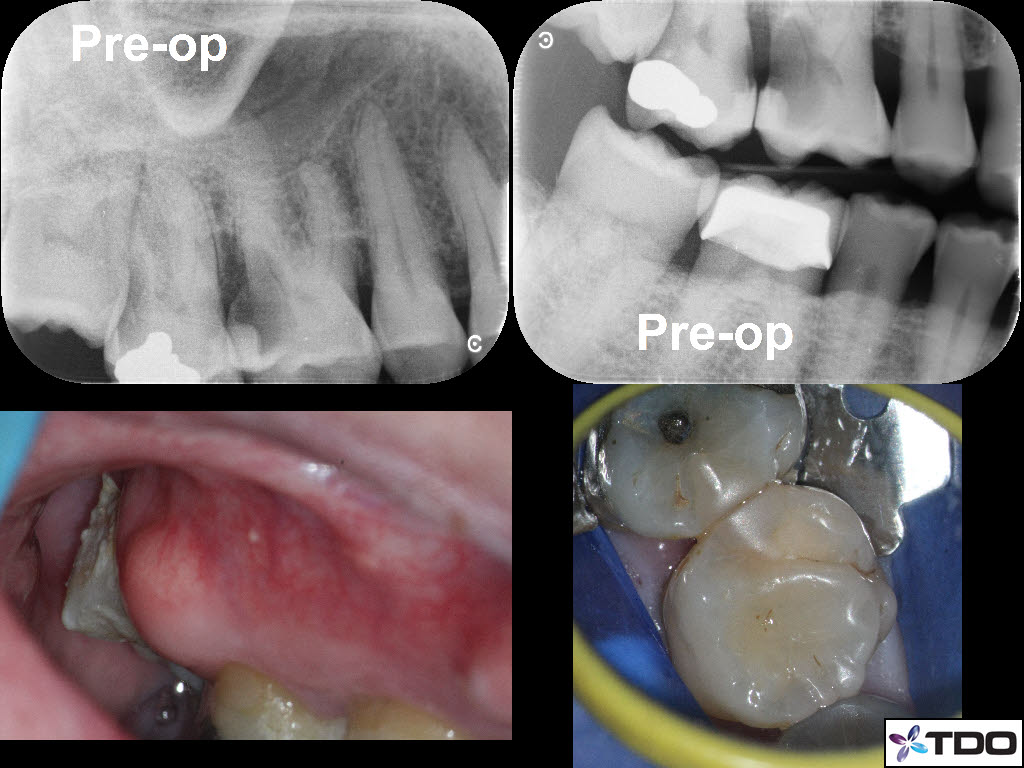

Restoring with Amalgam. 72yom. The patient had avoided the dentist due to dental anxiety. Tooth #3(16) SIP and #2(17) responded normally to all clinical tests. I recommended attempting to save both molars but he hesitantly agreed to start with tooth #3. Image Guided Treatment using CBCT aided in confirming the presence and location of MB2. The Opaldam matrix, first described by Dr. Michael Trudeau, is useful when using amalgam to restore teeth with deep interproximal caries especially when one or more corners are lost. In the end, the patient elected to extract the second and third molars and the amalgam restoration was incorporated into a Deep Margin Elevation for crown placement.